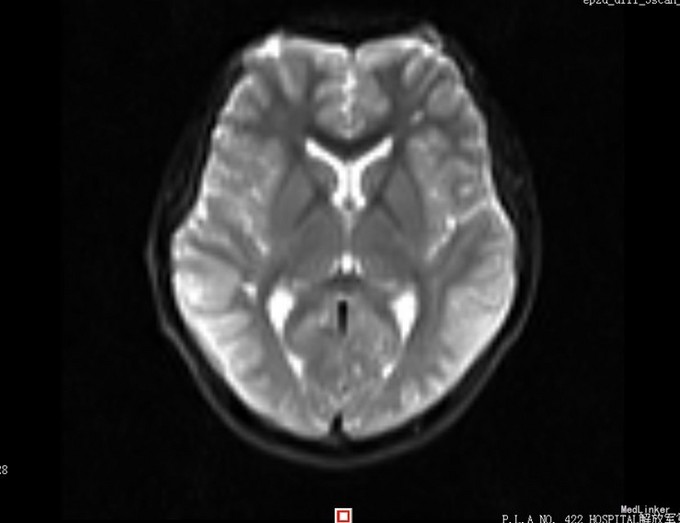

患者,男,14岁,患者自2周前不慎因外伤后出现头痛、头晕,为持续性钝痛,以后枕部为主,无发热畏寒,无视物模糊,无胸闷气短等不适,当时未引起足够重视,后患者感症状持续存在,遂告诉家人,家人送到我院门诊就诊,查头颅CT示:1、双侧大脑半卵圆中心区见多发斑片状低密度影,考虑血管间隙扩大可能,建议MRI复查;2、双侧额窦、筛窦炎。为进一步检查及治疗入院。患者目前精神欠佳,体力下降,食欲正常,睡眠正常,体重无明显变化,大便正常,排尿正常。既往体健。

患者目前诊断:1、脑外伤后综合征;2、半卵圆中心区血管间隙扩大;给予改善循环、营养神经等对症治疗,患者头痛、头晕症状明显好转。